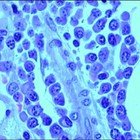

04/03/2013Un equipo médico de Estados Unidos ha anunciado lo que podría ser la primera cura completa de un bebé nacido con el VIH. Todo gracias a una intervención temprana, a las 30 horas de su nacimiento, con un tratamiento agresivo de tres antirretrovirales. Se trataría del segundo caso en el mundo, el primero en menores.